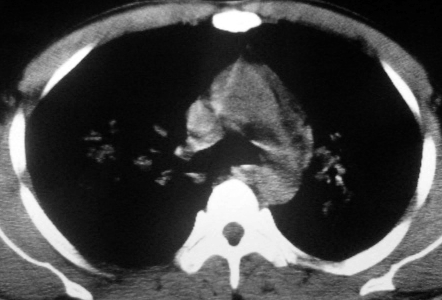

男,36岁,一月前醉酒淋雨后发热咳嗽,气短进行性加重.

抗生素治疗无效,痰检(一).

影像诊断:结核? 还有其他考虑吗?

双肺内中部见略不对称性蝶翼状高密度区,边界不清,部分呈磨玻璃样密度,并可见含气支气管征。肺门、纵隔内未见肿大淋巴结影。无胸腔积液。

双肺斑片状密度均匀病灶,边界模糊可见充气支气管征,上野多于下野,不支持结核,1肺内感染,2查肾功,中心型肺水肿待除外.

还是考虑肺水肿!蝶翼征.肺门增大,肺血管影增粗,!!病变累及中内带为主!要排外支原体感染.